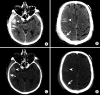

Intracranial hemorrhage is common and is caused by diverse pathology, including trauma, hypertension, cerebral amyloid angiopathy, hemorrhagic conversion of ischemic infarction, cerebral aneurysms, cerebral arteriovenous malformations, dural arteriovenous fistula, vasculitis, and venous sinus thrombosis, among other causes. Neuroimaging is essential for the treating physician to identify the cause of hemorrhage and to understand the location and severity of hemorrhage, the risk of impending cerebral injury, and to guide often emergent patient treatment. We review CT and MRI evaluation of intracranial hemorrhage with the goal of providing a broad overview of the diverse causes and varied appearances of intracranial hemorrhage.